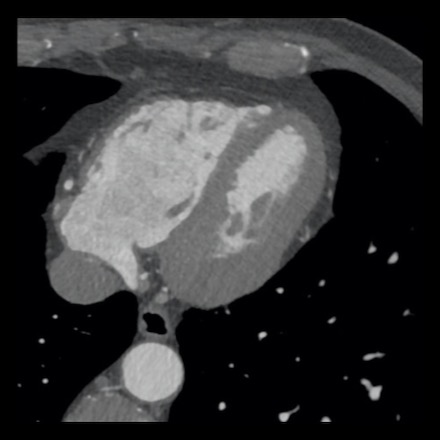

case 4 – CAD-RADS 3/P1/I+ thrombus left ventricle

First, scroll through the CTA images.

How would you describe the findings on the coronary CTA?

The findings are:

- Moderate (50-69%)

stenosis in the proximal LAD caused by a non-calcified plaque. - Variant of

sinoatrial (SA) nodal artery. The artery usually arises from the RCA as a second

branch after the conus artery, however in this case it arises from the LCX,

courses behind the aorta, anastomosing with the right atrium and with a small

branch supplies the SA-node of the heart. - Thrombus in the

apex of the left ventricle. - CTP was performed

in this patient. CTP showed a perfusion defect at stress imaging in the

territory of the LAD (I+), at rest no perfusion defect was visible.

This patient classifies as CAD-RADS 3/P1/I+, which means

this patient requires further investigation.

…

Same patient.

A: Curved MPR of the LAD with non-calcified plaque causing moderate (50-69%) stenosis.

B: The so-called “spider-view” (LAO caudal) of the heart with a 70% stenosis in the proximal LAD. Note the presence of SA nodal artery arising from the proximal LCX and coursing to posterior direction.

C: A drug eluting stent (DES) was implanted into the proximal LAD with good results.